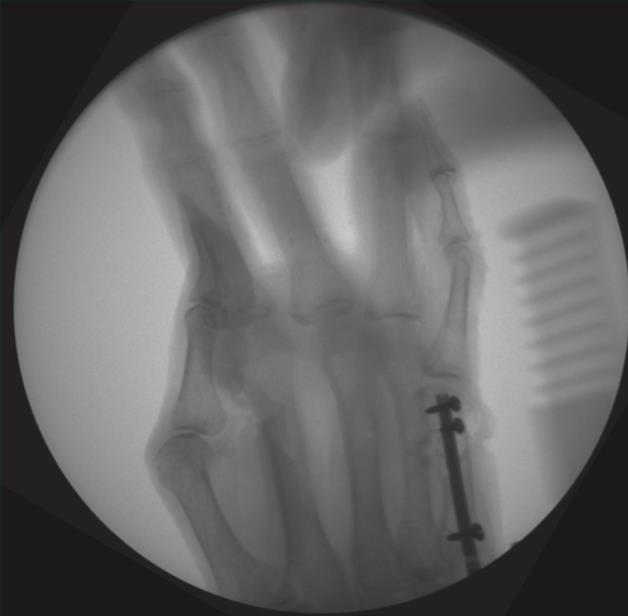

• step 3

• assemble the drill guide by inserting the metacarpal drill guide locking screw first, aligning the drill guide tabs with the cutouts on the nail, and fully tightening

• place the k-wire tip into the cupped front end of the nail and advance the nail into the medullary canal while allowing the k-wire to exit

• confirm fracture reduction and final nail position with fluoroscopy, ensuring the locking screw holes are not near fracture lines

• retighten the drill guide locking screw after nail insertion

• step 4

• insert a 1.4mm k-wire through the drill guide hole that is 5mm greater than the chosen nail length for distal provisional fixation

• insert a 1.4mm k-wire through the most proximal drill guide hole for proximal provisional fixation